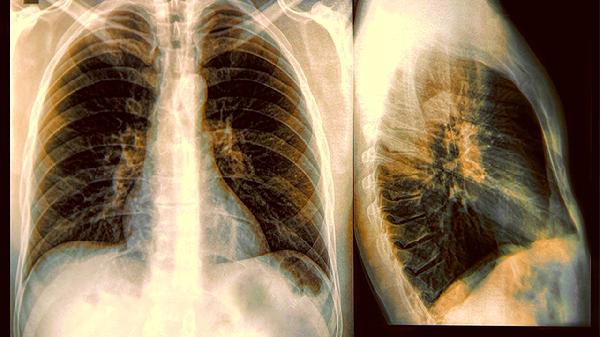

聽說體檢報告上出現”肺結節”三個字,很多人第一反應:該不會要變肺癌吧?先別急著嚇自己,肺結節其實就像皮膚上的小痣一樣常見。但為什麼有些人特別容易中招?原來身體早就悄悄給出了信號。